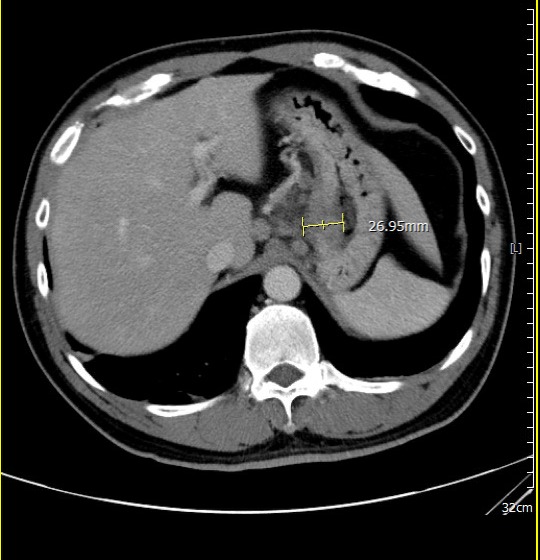

過去胃癌治療多以手術後化療為主,但近年研究已證實,術前治療能有效提升腫瘤可切除率。若術後病理組織中「完全找不到癌細胞」,稱為「病理完全反應」,通常與更低的復發風險及更理想的長期預後相關,已成為國際高度重視的治療指標。 腹部斷層掃描(治療前)

腹部斷層掃描(治療前)

在為期兩個月的術前免疫治療合併化療期間,病人雖出現噁心、掉髮、倦怠等副作用,但家人每日陪伴、鼓勵,使他能堅定完成療程。隨著治療進展,患者症狀逐漸改善,胃痛減緩、進食量增加、精神與體力明顯好轉,全家人的心情也從陰霾中逐步走出。 腹部斷層掃描(治療後)

腹部斷層掃描(治療後)